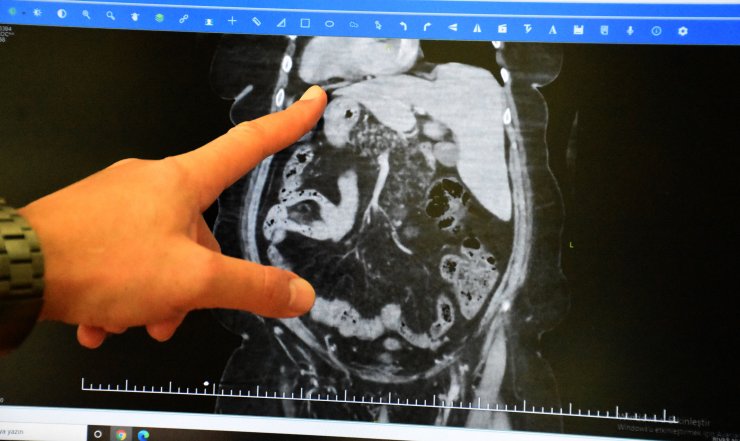

Sivas merkeze bağlı Budaklı köyünde yaşayan Nafia Koç, 2015 yılında muayene için gittiği hastanede iç organlarının ters yerleşimli olduğunu öğrendi. Bu zamana kadar organlarının ters yerleşimli olmasından endişe duymayan Koç, 2 ay önce karın ağrısı şikayetiyle Numune Hastanesi'ne başvurdu. Safra kesesinde taş olduğu belirlenen Nafia Koç için ameliyata karar verildi. Koç, genel cerrahi uzmanı Dr. Gündüz Akgöl ve Dr. Tarık Recep Kantarcı tarafından ameliyat edildi. Cerrahların ameliyat öncesinde yaptığı literatür taramasında Koç'un, dünyada ters organlı safra kesesi ameliyatı olan 81'inci kişi olduğu belirlendi. Nadir görülen durum için endişe eden hastanın ameliyatı ise başarılı geçti.

Ameliyatla ilgili bilgi veren Dr. Gündüz Akgöl, "Hastamızın özel bir durumu vardı. Doğuştan göğüs ve karın içindeki organların tamamen ters yönde yerleşimliydi. Normal insanlarda kalp solda olur ama bu hastamızda sağda. Karaciğer ve safra kesesinin sağda yerleşimli olması lazım. Bizim hastamızda sol tarafta. Dalak ise solda olması gerekirken sağda. Hastamız bu durumunu daha önceki yapılan tetkiklerde saptandığı için biliyordu. Bu hastamız safra kesesinde taşa bağlı karın ağrısı şikayetleriyle bize başvurdu. Safra kesesinde taş olması nedeniyle ameliyat planladık. Ameliyat hazırlıkları sırasında literatürü taradık. Bu organ tersliği durumu yaklaşık 30 bin kişide bir görülen çok ender bir durum. Bu hastalarda safra kesesi taşı olması da çok nadir görülen bir durum. Yine literatürü taradığımda 80 tane organları ters hastaya kapalı safra kesesi ameliyatı yapılmış. Bugüne kadar dünya genelinde yayına geçen 80 tane hasta görülüyor. 2014 yılında bu ameliyattan bir tane daha yapmıştık. O zamanlar yayınlanan 40 hasta vardı. Son 8 yılda bu literatüre 40 hasta daha girmiş. Bizim hastamızda bu aşamada 81'inci oluyor. Bu hastamızın organları ters olduğu için şimdiye kadar yaptığımız tüm ameliyatlardan farklı olarak kapalı ameliyatta aletlerin yerleri değişti. Kullandığımız cihazların konumları biraz bizi zorladı. Çünkü sağ elimizle yaptığımız işi bu sefer sol elimizle yapmamız gerekti ve pozisyonlarda farklılıklar oldu. Bu açıdan ameliyatı kapalı yapmak önemliydi. Tecrübelerimizde bu ameliyatı hallettik. Ameliyatımızı başarılı bir şekilde bitirdik" diye konuştu.